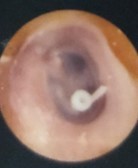

Grommet (tympanostomy tube)